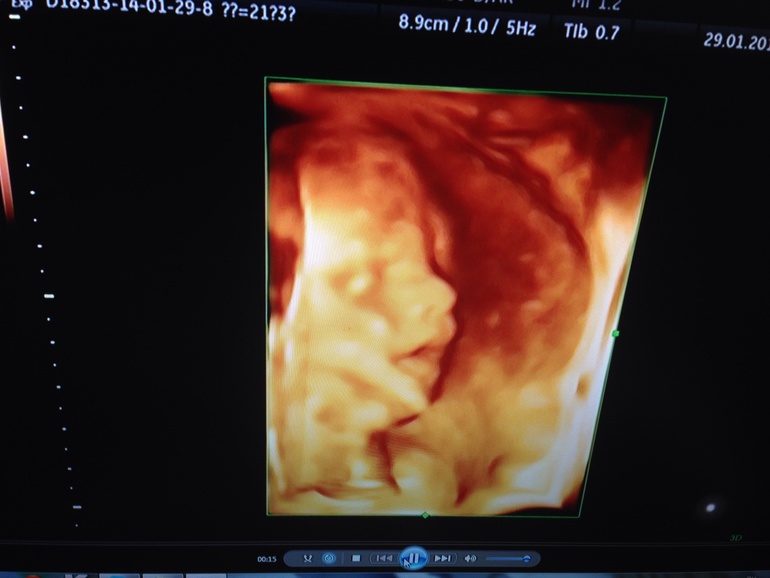

Ну и наш пузик)

Шевеления активные, икота у малыша появилась)

И сидит наш пацан на попе (в прошлый раз лежал поперек), разговариваю с ним, объясняю, что надо б перевернуться, но время еще есть, думаю сам знает когда и как повернуться) точнее надеюсь)) такие вот дела) чувствую, скоро понесет меня за покупками вещичек мальчуковых))) а пока наслаждаюсь своим положением)